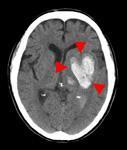

頭部CT検査

十数秒の撮影で、脳内の状態を知ることできます。

画像例では、脳の正常部分に対して白く描出されている部分があることで、脳内出血、くも膜下出血が起きていることがわかります。

反対に、黒く描出されている部分があることで、脳梗塞が起きていることがわかります。

画像の濃淡を調整すると、頭蓋骨骨折の有無を確認することもできます。

また、造影剤を注射しながら撮影することで、動脈瘤や腫瘍などのより詳細な観察が可能になります。